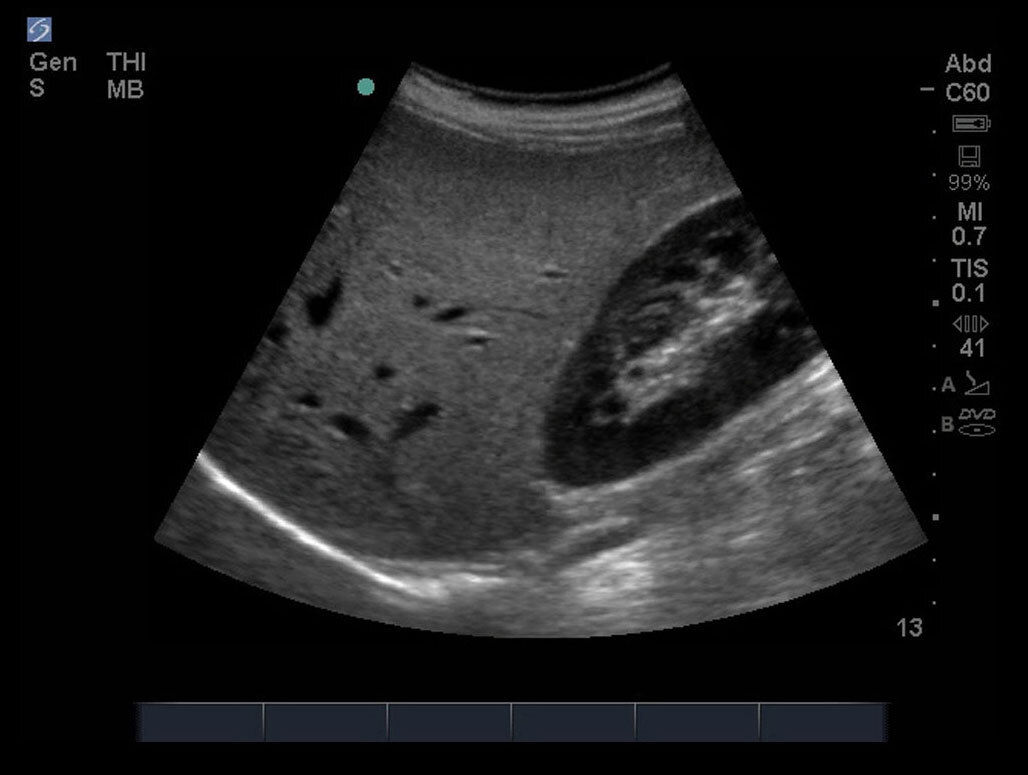

FAST 右上四半部 (RUQ) 5 画像

M-Turbo